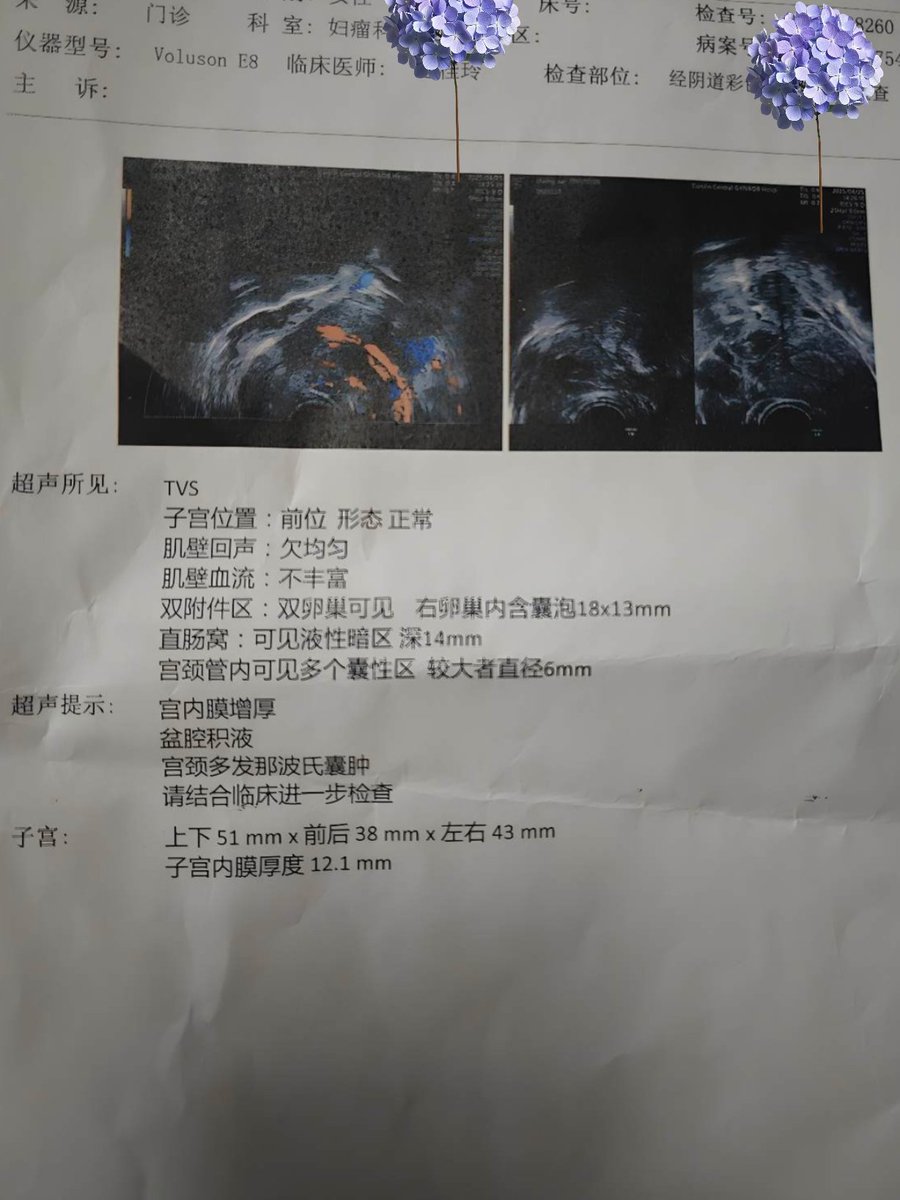

地狱难度…救救我TT

目前好像还没有找到能治好的办法,脊椎的疼痛和内异症的都是。有一个关键字为血小板的治疗3k一针…不知道要做多少次,而且似乎也不确定效果

开了住院的单子但是还没决定要不要去。好想放弃啊…明明这样更轻松,坚持下去的理由到底是什么根本想不出来,为什么大家都说活着是正确的 https://t.co/aBYikEDvqG